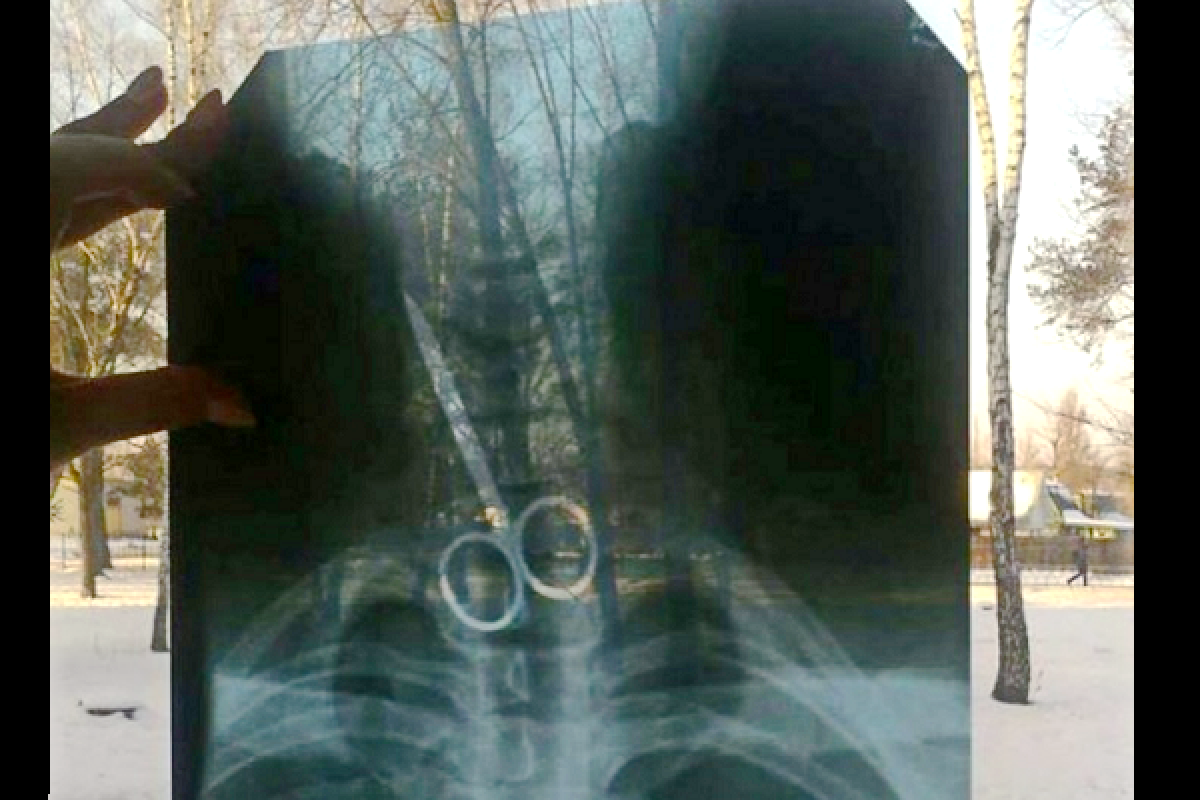

К врачам Черниговской областной больницы обратился местный житель с просьбой осмотреть его. Медики сделали рентген, который показал, что в желудке пациента находятся металлические предметы - ножницы и ложка.

Сейчас имя и возраст мужчины не разглашаются. Однако, стало известно мотив такого поступка. Так, черниговец проглотил предметы на спор.